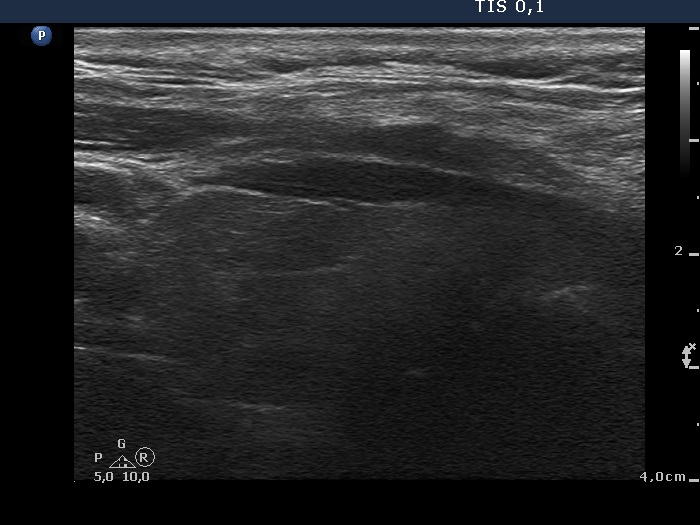

Anaplastic carcinoma - Case 12. (ultrasonographic picture 2)

Right lobe, longitudinal scan.